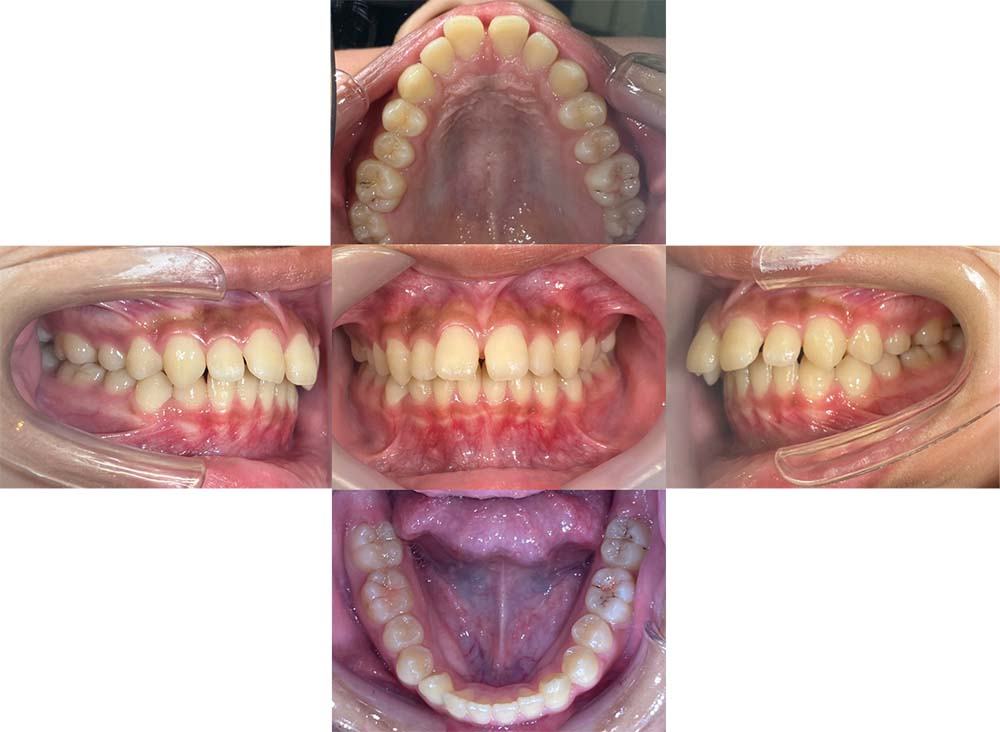

症例02

| 主訴 | 下あご顎が出ている。曲がっている。 |

| 診断名あるいは主な症状 | 反対咬合、非対称、空隙歯列、過蓋咬合 |

| 年齢/性別 | 19歳・女性 |

| 矯正ステージ | 大人の矯正治療 |

| 治療方法 | ワイヤー矯正、顎矯正手術の施行 |

| 抜歯部位/抜歯有無 | 非抜歯 |

| 治療内容 | 上下顎歯列を並べた後に顎矯正手術の施行。 |

| 費用 | 保険治療 |

| 治療期間 | 3年2ヶ月 |

| 主なリスク・副作用 | 痛み、歯根吸収、歯肉退縮、虫歯、後戻り |